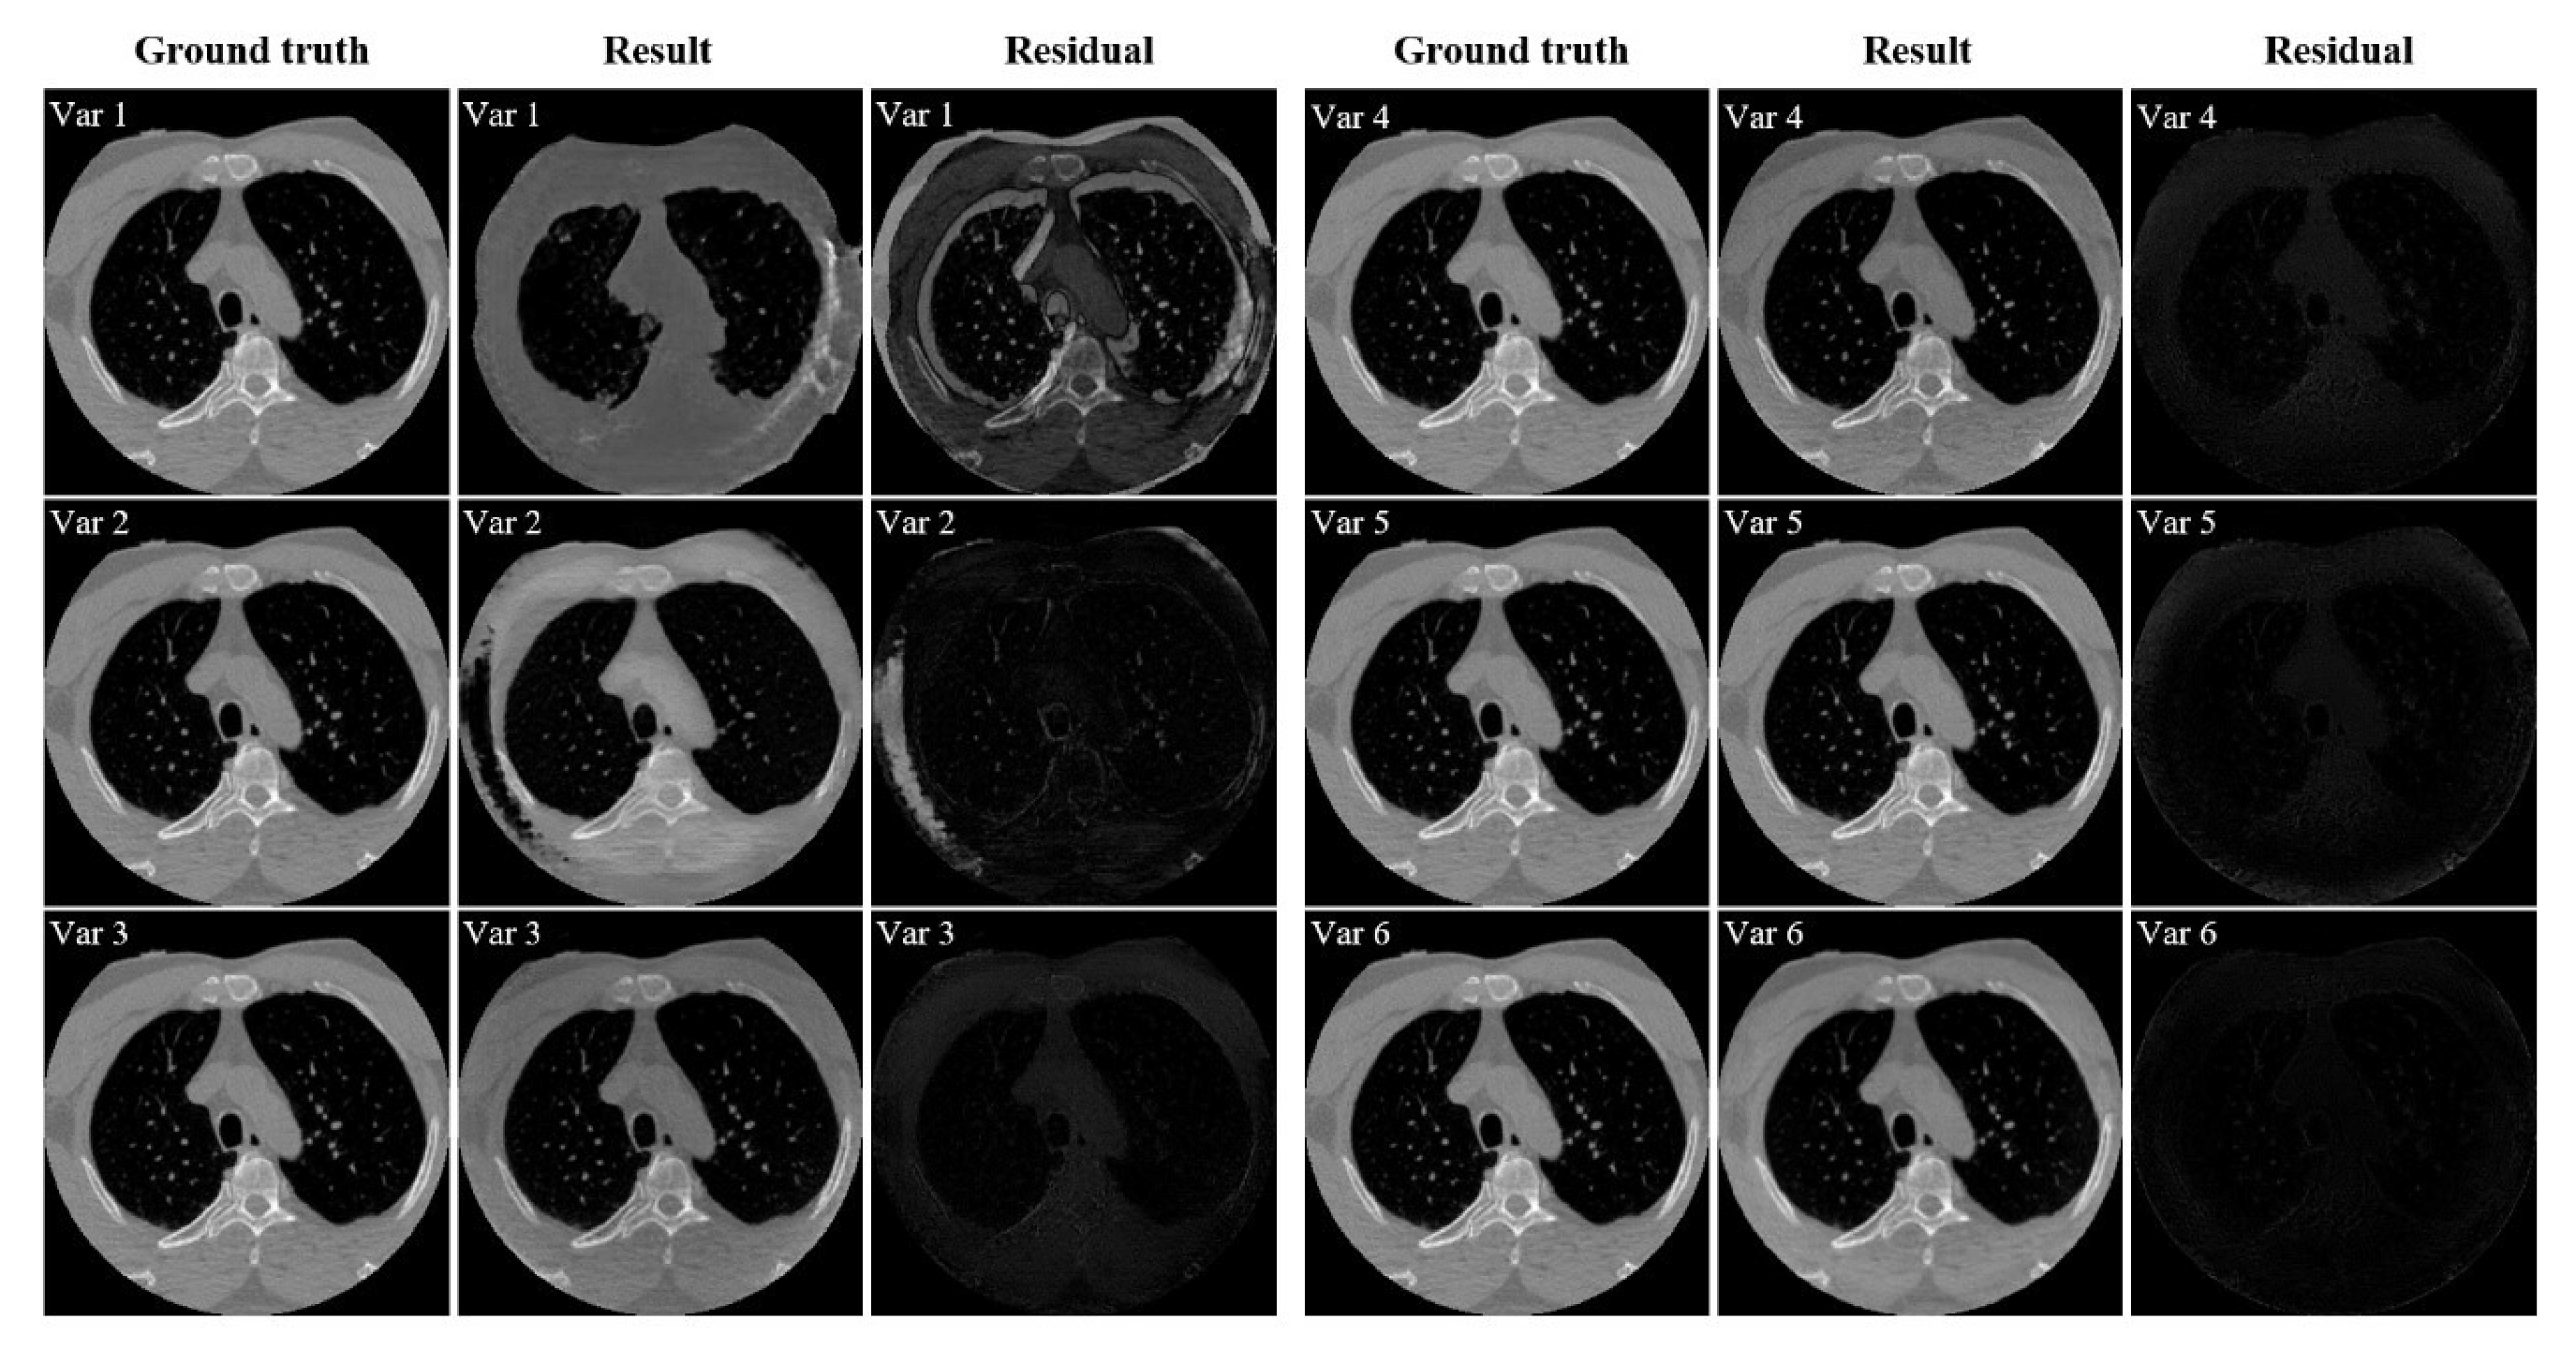

3.5.1. Performance of Model Components

To validate the effectiveness of the different components in our proposed model, six ablation experiments were conducted on dataset CL1. The configurations of the experiments are shown as follows:

- Var1: only the adversarial loss is introduced in the network.

- Var2: the reconstruction loss is added to Var1.

- Var3: the artifact consistency loss is introduced to Var2.

- Var4: the cycle consistency loss is added on the basis of Var3.

- Var5: the polar coordinate transformation is incorporated into Var4.

- Var6: the total variation loss is added to Var5, and this is the final network configuration.

Table 4 shows a significant increase in SSIM and PSNR scores from Var1 to Var6. Var1, having only discriminative constraints, fails to recover many image details. However, when introducing the reconstruction loss in Var2, the network’s performance notably improves. At this stage, the network’s performance surpasses that of the classical unsupervised Cycle-GAN model. Subsequently, with the inclusion of artifact consistency and cycle consistency losses, the network’s performance sees a marked enhancement over Var2. SSIM increases by nearly 5 percentage points, and PSNR improves by approximately 4.6 dB. To further optimize the network, the polar coordinate transformation is incorporated in Var4, forming Var5. The performance metrics of Var5 show further improvement, indicating that polar coordinates indeed help enhance the separation of artifact features and content features. Finally, with the addition of lateral TV constraints in Var6, compared to Var4, SSIM increases by 1.6 percentage points, and PSNR improves by nearly 4 dB. These results demonstrate the effectiveness of polar coordinates and the lateral TV constraint. Consistent with Table 4, the residual images from Var1 to Var6 in Figure 10 are getting smaller, confirming that all introduced constraints and tricks significantly contribute to improving network performance.

Figure 10.

Qualitative analysis of the ablation study of the proposed PIDNET conducted on dataset CL1. Var1–Var6 mean different components added to the network. Each group’s three columns represent ground truth, resulting image, and residual image, respectively.